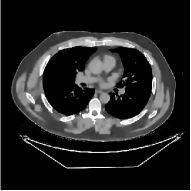

This paper was inspired by a simple observation related to our recent study [34]: for the penalized weighted-least squares (PWLS) reconstruction method using prior with a learned ST (PWLS-ST-) [34], the sparsification error histograms match a Laplace distribution over the iterations; see Fig. 1. The question then arises, “Does the learned prior experience model mismatch in testing stage?” To answer this question, we aim to investigate learned STs for regularization. This paper

The term denotes a -based sparsification error [3, 4, 5]. We expect to be more robust to sparsity model mismatch than the -based sparsification error used in [34, 36]. Fig. 1 shows histograms of sparsification error at different outer iterations of the PWLS-ST- method. Over the iterations, the sparsification error histograms appear more like a Laplace distribution than a Gaussian distribution. This observation suggests that the proposed prior model is more suitable than the prior model for PWLS-ST-based reconstruction. Section III-B1 shows that the proposed -based sparsification error term, , improves the accuracy of reconstruction compared to the prior model in [34, 36].